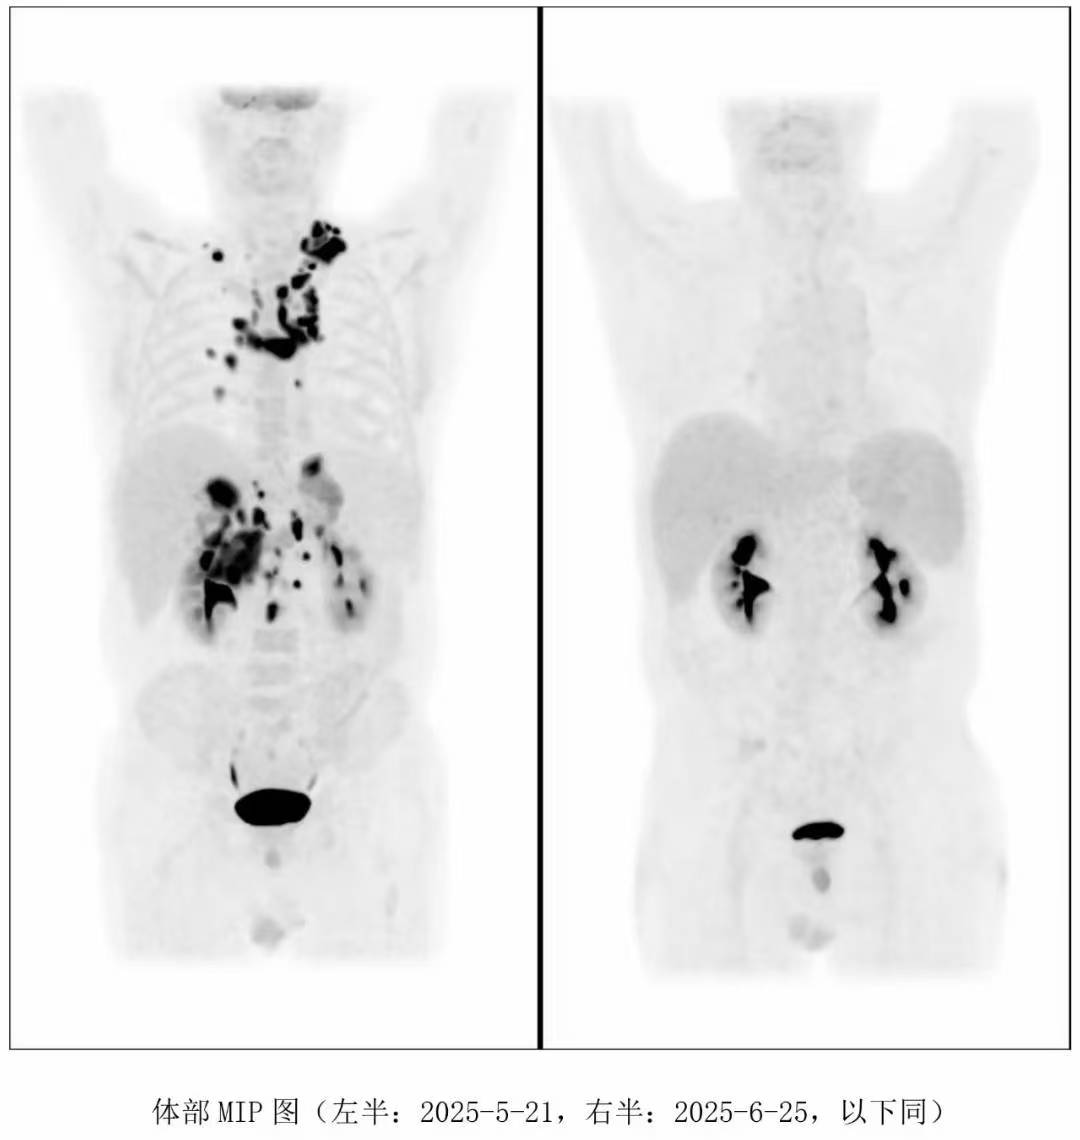

2025 年 4 月,老马无诱因再次发热,是的,肿瘤不出意外地又回来了,PET-CT 复查显示疾病进展,怎么办?还有什么方案?

b563a4543d9db1ef22950f58d3248db6.png

25年5月底进仓,6月初陆续回输了半相合的儿子干细胞以及脐带血细胞,6.25出仓,PET-CT评估,完全缓解!

26727c097af6ae8b6bb0027b0cbb11fc.png